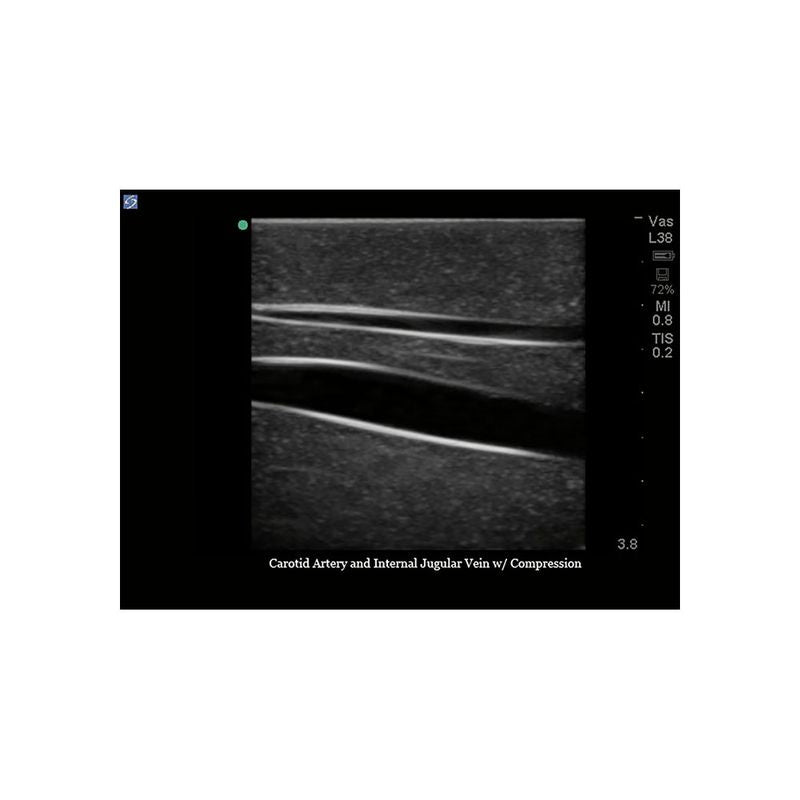

Replacement tissue insert for Central Line and Regional Anesthesia Model (BPHNB670 series).-